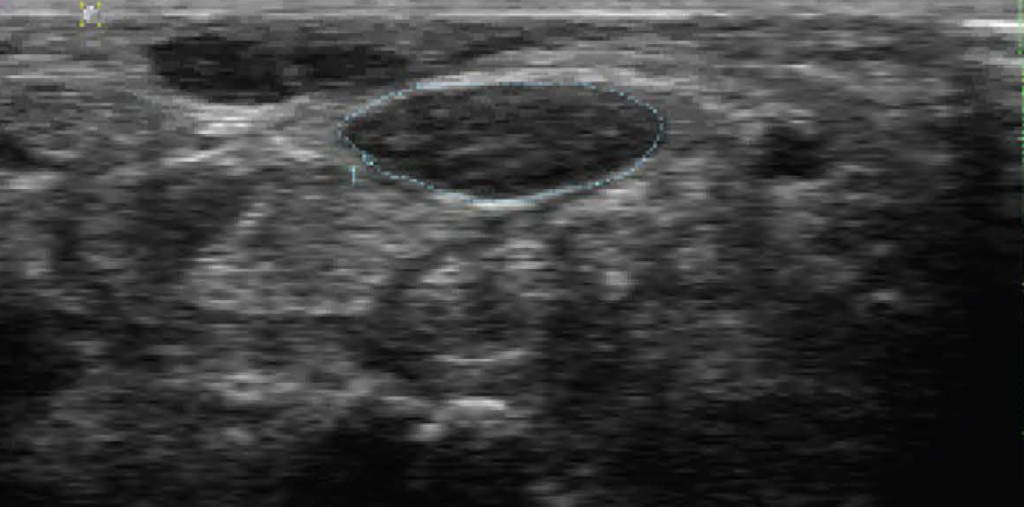

carpal tunnel syndrome

I recall from medical school days that we were given the impression that carpal tunnel syndrome is caused from narrowing of the carpal tunnel and the only treatment option for carpal tunnel syndrome is surgical decompression. Of course, the “narrowing” can be caused by many different conditions (see below). It’s pretty customary these days that we need to explore the aetiology of the CTS with an ultrasound. Clarification of the anatomy may open up the option of injections to relieve symptoms.